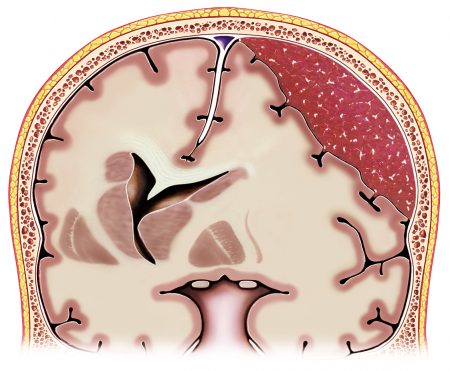

subdural-hamatoma-st-louis-doctor

Craniotomy for Epidural Hematoma

Craniotomy for Subdural Hematoma